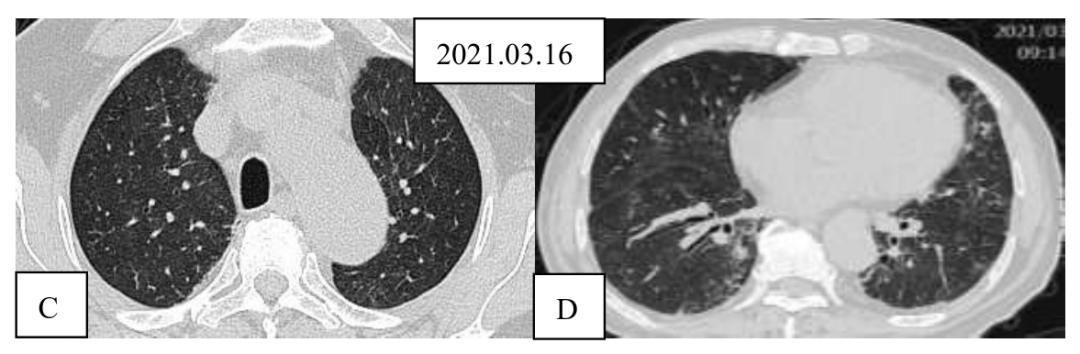

图2肺组织标本病理图HE(A)染色示肺泡间隔增宽,免疫组化染色示间质淋巴细胞浸润(B),肺泡内吞噬细胞聚集(C)。4.转归:3月16日(激素治疗7天后)复查胸部CT两肺间质性炎症,两肺下叶局部支气管扩张。病灶较前明显吸收。

图3激素治疗前后胸部CT平扫对比图上行,激素治疗前主动脉弓(A)及下肺静脉(B)层面CT表现;下行,激素治疗1周后,主动脉弓(C)及下肺静脉(D)层面CT,示双肺磨玻璃影较前明显吸收。5.手术:经治疗10天,患者已无明显活动后气促。复查血气分析,患者呼吸空气时,PaO2可达85 mmHg。激素治疗已减量为口服强的松30 mg/日。患者转回骨关节科,2021.03.26在全麻下行右侧髋关节滑膜切除术+右侧髋关节松解术+右侧髋关节置换术,术后恢复良好。

答:基于人群的研究显示,约5%-10%的RA病例发生临床明显的ILD。RA-ILD中UIP为主要病理类型(56%),其次为NSIP(33%),机化性肺炎(11%)[1]。从影像学特征分析,RA-ILD阳性患者常见的肺部改变是网格样改变(57.8%),胸膜增厚(57%),磨玻璃样改变(53.2%)。与RA-ILD阴性患者相比,RA-ILD阳性患者出现胸膜增厚(57.0% vs. 28.1%),支气管扩张(18.1% vs. 10.5%),支气管血管束增粗(35.4% vs. 9.6%)和肺动脉高压(9.4% vs. 3.6%)的比例明显增加,两组相比出现肺大泡、肺部结节和胸膜下结节的比例则没有统计学差异。这名患者的胸部CT扫描显示主要为双肺磨玻璃影,病灶沿气道累及更明显,双下肺有支气管扩张改变,而无典型蜂窝。此外,患者激素治疗后短期内病灶吸收。这些特征都不同于典型RA-ILD的特征。

Q4:这名患者对激素治疗反应特别好,影像学主要表现为双肺磨玻璃影,少量支气管扩张影,无明显蜂窝,而且复查CT示双肺磨玻璃影短期内迅速吸收,这与经典的RA的影像学及治疗反应不符合。冷冻肺活检病理也显示这名患者肺部病理改变不是UIP或NSIP,而是HP,那么临床上我们怎么诊断HP,这个疾病的病理特征如何?